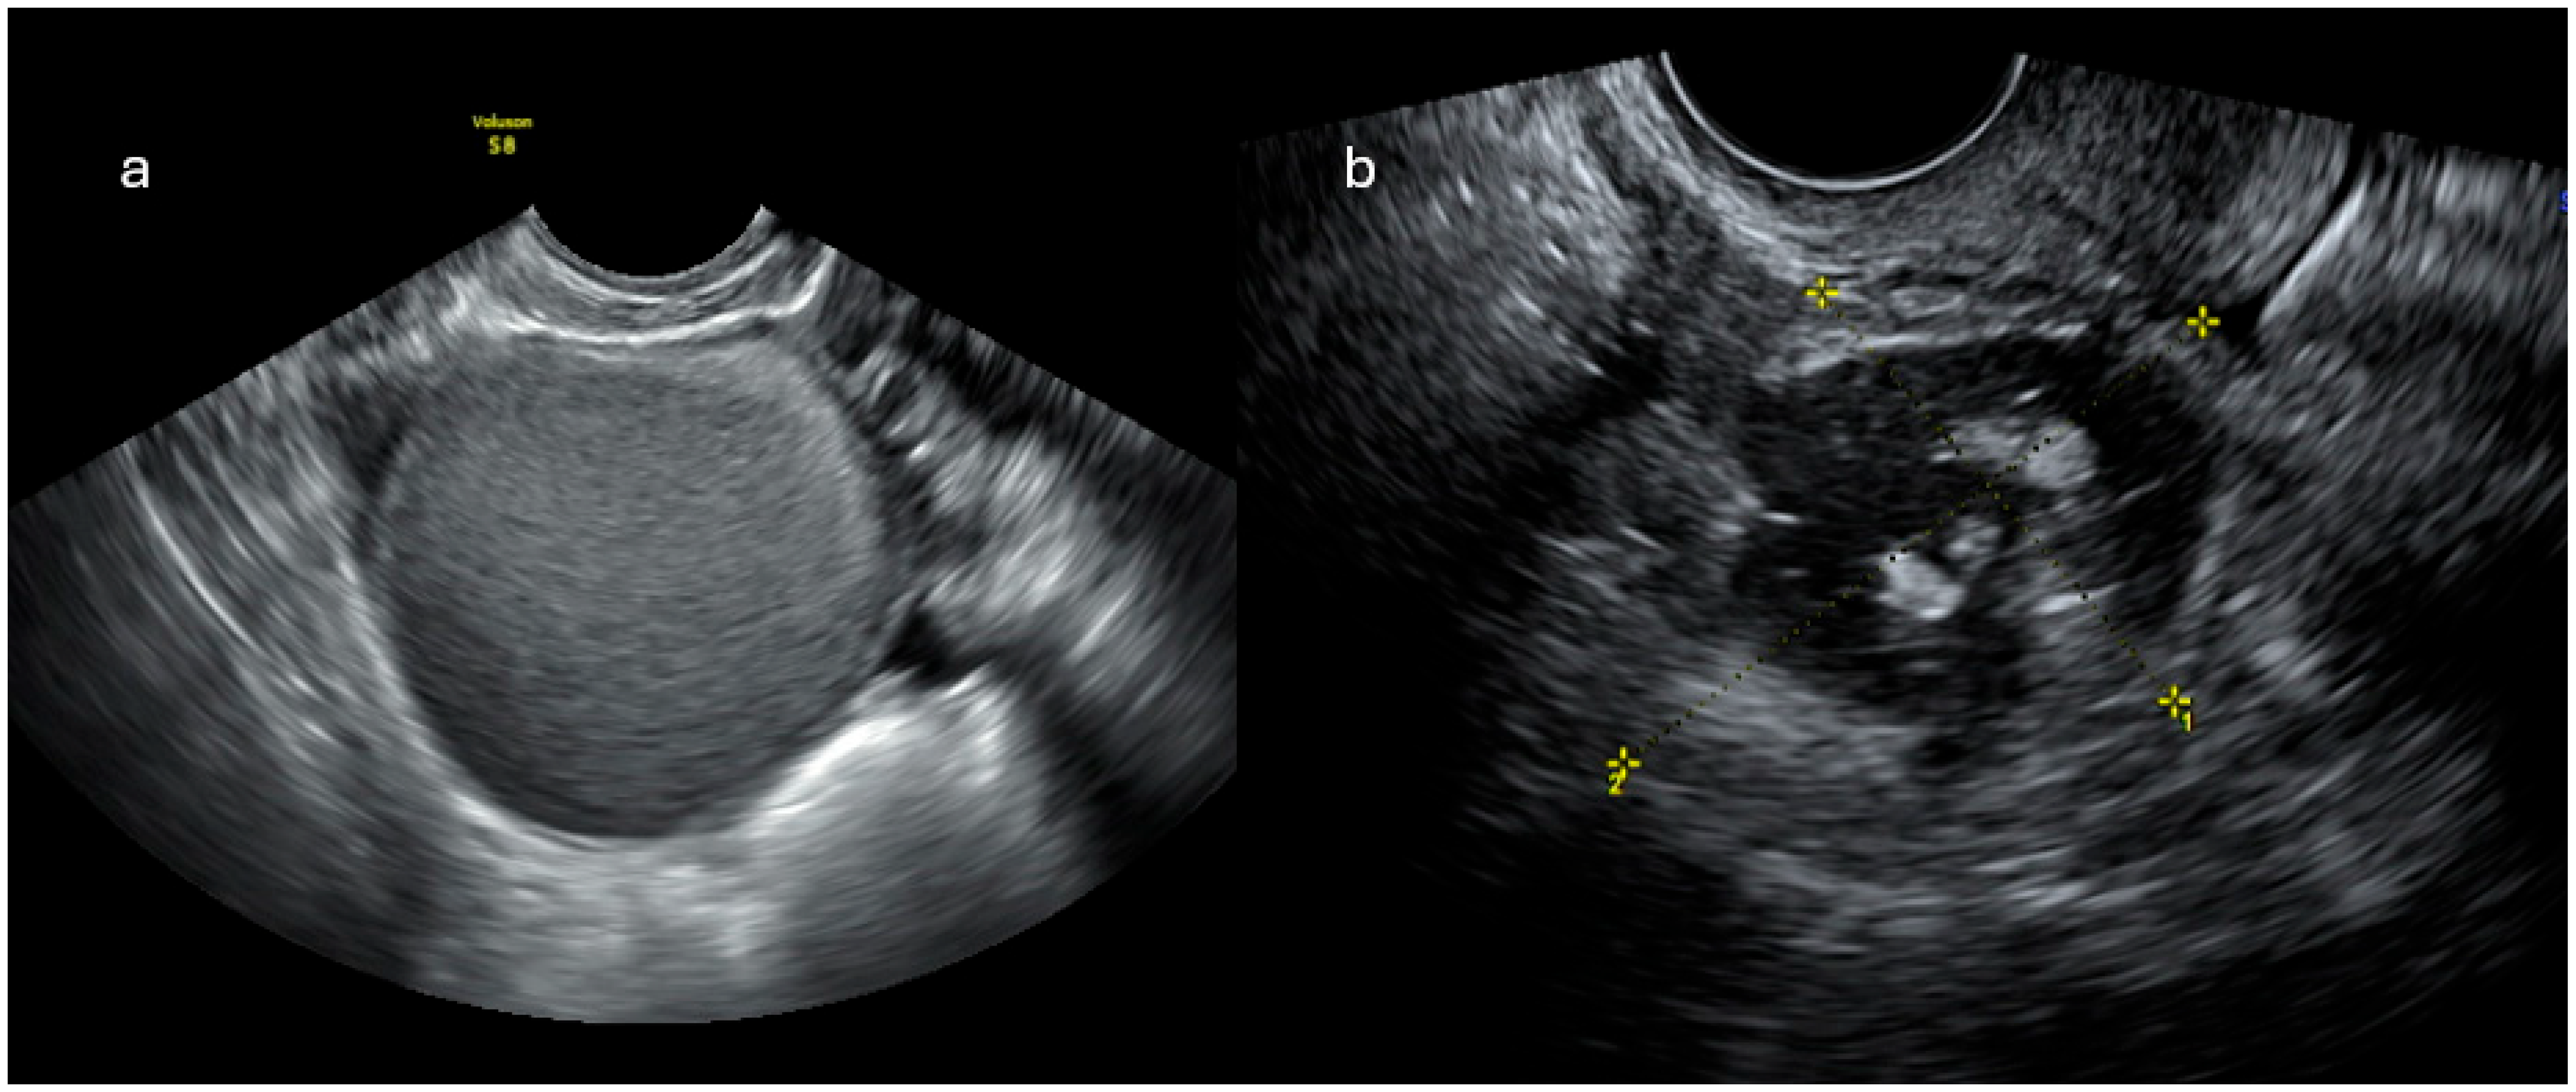

2.1. Ultrasonographic Imaging

2.1.1. IOTA ADNEX Model

2.1.2. O-RADS US

- O-RADS 0: technically inadequate/not applicable

- O-RADS 1: physiological findings; no ovarian lesions

- O-RADS 2: lesions almost certainly benign (<1% risk of malignancy)

- O-RADS 3: lesions with low risk of malignancy (1–10%)

- O-RADS 4: lesions with intermediate risk of malignancy (10–50%)

- O-RADS 5: lesions with high risk of malignancy (>50%)